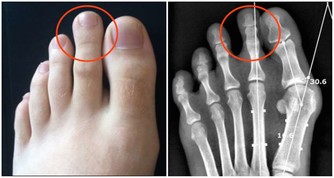

對於治療中西醫束手無策的痛風,卻有令人無法想像的療效,只要早晚飲用一顆新鮮椰子水,即使痛風情況嚴重到骨關節變形,依然可以康復。

許多患者只有血清尿酸鹽濃度的增高而沒有臨床症狀,只有在發生關節炎時才稱為痛風。痛風的病理基礎是高尿酸血症,正常人血尿酸值是男性2.4-7mg/dL,女性1.6-5.2mg/dL。

當體液中尿酸濃度超過此值時,將因過剩而在組織中沉積,這種尿酸鹽的結晶沉積在關節滑膜、關節骨、軟骨而導致痛風性關節炎,沉積在皮下則形成痛風石。中西醫均會要求痛風患者不可以攝取高普林食物,然而這些食物可以說是最起碼的美食,要痛風病患完全不吃這些食物,說真的,這種治療的犧牲代價還不小呢!